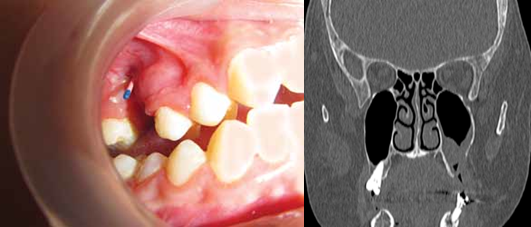

4)种植牙或者种植体

显示种植体和上颌窦植骨移位

种植牙:评估种植体周围炎或移动种植体

2)确诊后需要仔细评估,如何处理,先处理牙齿问题还是优先处理鼻窦问题?种植牙是否可以保留?